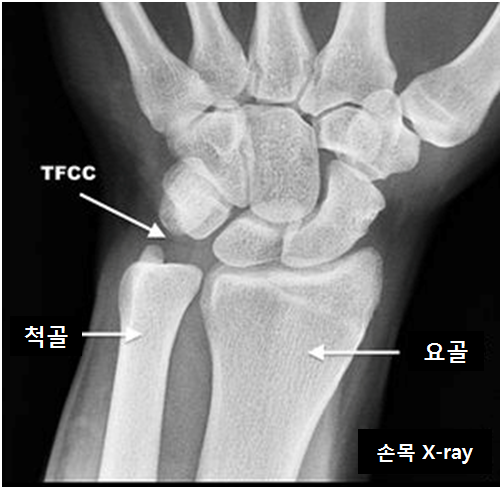

수부에서 가장 흔하게 볼 수 있는 손상중에 하나가 바로 삼각섬유연골 복합체의 손상입니다. 정형외과에서는 TFCC 손상이라고 흔히들 약어로 부르게 됩니다. 이는 요수근 관절에서 원위 요척관절은 회내, 회외 운전의 축(Pivot) 역할을 하는 곳입니다.

이들의 기능은 척골두를 덮어 원위 요골의 관절면이 연장되게 하며, 척수근 관절에 부하되는 힘의 일부를 흡수하고, 전완부의 회전시 척골과 요골을 결합시키며, 척골과 요골을 연결시켜 척측의 수근골을 지지합니다. 척골 경상돌기 골절이 동반될 수 있으며, 원위 요척관절, 척수근관절과 기능적, 구조적으로 연결되어 있으므로 주의깊게 관찰하여야 합니다.

영산 진단으로는 X-ray 보다는 MRI를 이용해 볼 수 있습니다. 조영제 주사 후 영상을 얻을 경우 파열된 삼각 섬유연골 복합체를 통해 조영제가 투과되거나 파열된 부위에 저류(pooling)되는 것으로 더 민감하게 지단할 수 있습니다. 골절이나 관절의 변형은 CT가 이용되며 삼차원 영상으로 재건할 경우 요골과 척골의 관계를 파악하는데 도움이 많이 됩니다. 또한 진단과 치료를 위해서 관절경이 널리 이용되는데, 삼각 섬유연골 복합체의 파열이나 척골두와 수근골의 연골연화증을 가장 정확하게 진단할 수 있습니다.